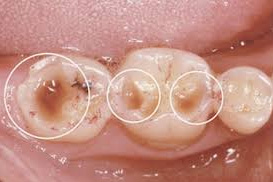

臼歯部のファセット

噛み合わせの力によって、歯がすり減り、歯が平らになってきます。

咬耗

自分の歯がすりへってきます。